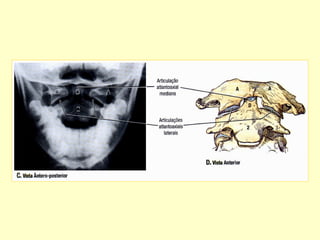

Para avaliação da articulação

atlanto-axial por radiografias

convencionais. Realizar incidência

A. P. com boca aberta e perfil.

ARTICULAÇÃO ATLANTO-AXIAL

ARTICULAÇÃO

ATLANTO-AXIAL

1-membrana tentorial

2-ligamento apical

3-atlanto-occipital lig.

4-lig long. anterior